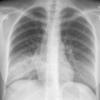

Case 1 Round pneumonia

Date: 04/16/2005

Views: 8017